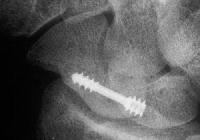

Xray before

and two months postop: